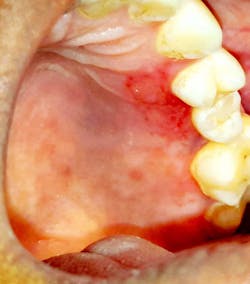

Case no. 1

The provisional diagnosis was COVID-19–related oral lesions. The case was managed using topical triamcinolone acetonide (Kenacort) 0.1% paste, doxycycline and benzalkonium chloride mouthrinse, and topical lignocaine 2% gel three times per day.

- Multiple palatal and oropharyngeal petechial lesions

- Palatal and oropharyngeal erosions and ulcerative lesions

- Severe pain over the lesion area

- Partial paresthesia surrounding the lesions

- Irregular areas of blanching involving the palate

- Burning sensation of palate and oropharynx, and dysphagia

- Palatal and oropharyngeal tenderness and soreness

- Necrotic pseudomembranes covering the erosive/ulcerative lesions